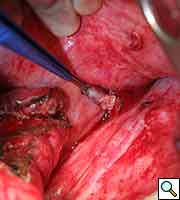

Flexible bronchoscopy revealed normal bronchial anatomy (Video 1). There was no evidence of stricture. All segmental airways were present. A right thoracotomy was performed. The sequestration appeared as a bluish mass incorporated in the substance of the right lower lobe (Figure 6). The artery supplying the sequestration was visualized coursing through the inferior pulmonary ligament and divided (Figures 7, 8; Video 2). Alternating single and double lung ventilation, the sequestration was identified along the basolateral margin of the right lung (Video 3) with a clear line of demarcation. A combination of electrocautery and 4.8mm endoscopic staplers (Video 4) was used to separate normal lung from the sequestration (Video 5). Fibrin glue was applied to all staple lines. Normal bronchial airways were not divided and the remaining lower lobe inflated normally (Video 6). The post-surgical course was uncomplicated and the patient was discharged on post-operative day four. Pathology revealed parenchymal cyst formation with chronic inflammation and organizing pneumonia.

| Figure 6: Intraoperative image of bluish-hued sequestration | Figure 7: Feeding artery ligated and partially divided | Figure 8: Cut end of feeder artery off aorta |